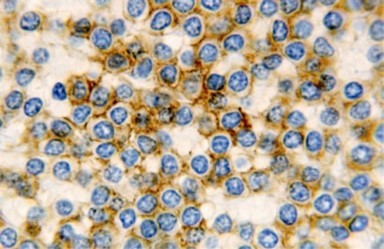

The leukaemia cells may enunciate a characteristic immune phenotype, crucial for a confirmatory diagnosis. The peripheral blood mononuclear B cell population may display a kappa or lambda light chain restriction. The phenotype of classic hairy cell leukaemia may be delineated by concurrent, immune reactive CD19+ CD20+,CD 11c+, CD25+, CD103+ and CD123+. An intensely immune reactive CD200+ and a non reactive CD27- antigen may be present2, 4. Evaluation of a trephine bone marrow biopsy and bone marrow aspirate may define the degree of tumour infiltration. A dry tap on account of prominent bone marrow fibrosis may be elucidated at preliminary diagnosis. A decline in the normal haematopoiesis may account for a hypo-cellular marrow in 10% instances. Gradation of cellular infiltrating of the leukaemia within the bone marrow may be appropriately investigated with immune –histochemical stains2, 4. Immune staining for CD20+, annexin 1 and VE1 (a BRAF V600E stain] may validate the diagnosis and precisely analyse the extent of malignant bone marrow infiltration[8]. Determination of BRAF V600E mutation may be critical in therapeutically non responsive individuals with applicable standard therapy or in instances of multitudinous reoccurrences[9]. Deploying inhibitors of BRAF V600E gene may be efficacious in patients impervious to approved therapy. The mutation necessitates a comprehensive scrutiny of the implicated individuals with a sensitive molecular assay which may discern up to < 10% of the hairy leukaemia cells appearing in the peripheral blood smears or bone marrow aspirates diluted with peripheral blood or aspirates elucidating a dry tap[2,4]. Allele specific polymerase chain reaction (PCR) or a next generation sequencing may be optimally employed to circumvent false negative outcomes. If the leukaemia cells are sparse or if particularly sensitive & efficacious molecular techniques are not accessible, the application of appropriate immune histochemical stains to the bone marrow biopsy such as a BRAF V600E mutation stain (VE1) may detect the hairy cells and conclusively diagnose the condition[2,4,10]. Figure 1, Figure 2, Figure 3, Figure 4, Figure 5, Figure 6, Figure 7, Figure 8, Figure 9, Figure 10, Figure 11, Figure 12, Figure 13, Figure 14.

Figure 1.HCL: hairy cells infiltrating designated spaces(17).

Figure 2.HCL: hairy cells with projecting cytoplasm abutting bony trabaculae(18).

Figure 3.HCL: hairy cells dispersed within the native architecture(19).

Figure 4.HCL: hairy cells with widely spaced nuclei(20).

Figure 5.HCL: hairy cells with infiltration in the spleen(21).

Figure 6.HCL: disseminated hairy cells with a clear cytoplasm(22).

Figure 7.HCL: blebs on the cellular surface with fine nuclear chromatin(23).

Figure 8.HCL: widely disseminated hairy cells within the bone marrow trabaculae(24).

Figure 9.HCL: hairy cells within a bone marrow trephine biopsy(25).

Figure 10.HCL: inconspicuous nucleoli, open-ended chromatic and surface protrusions(26).

Figure 11.HCL Oral mucosa with soft tissue infiltration of hairy cells(27).

Figure 12.HCL: hairy cells with broad and fine projections of the cytoplasm(28).

Figure 13.HCL: hairy cells immune reactive for CD 11c(24).

Figure 14.HCL: hairy cells with demonstrable tartrate resistant acidic phosphatise( TRAP) stain(29).